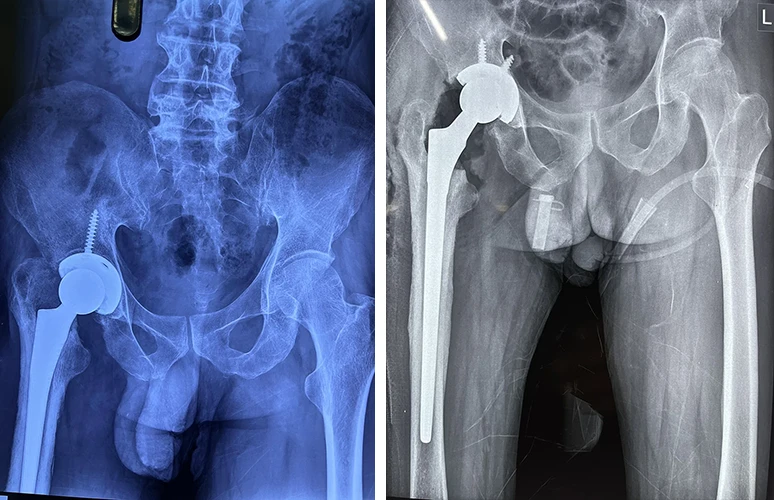

Total Hip Replacement

Are your hips causing you constant discomfort? If you're tired of living with hip pain, Dr. Prasun Sanyal is your best solution.